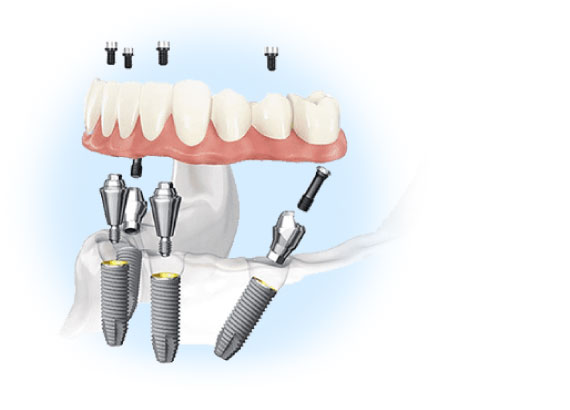

Медицинский центр «Интердентос» основан в 1998 году. Наши стандарты технического оснащения и контроля качества, подбора и подготовки врачей, защиты пациентов от инфекций являются чрезвычайно высокими, что подтверждено независимыми экспертами в области стоматологии. У нас работают дипломированные специалисты, оказывающие весь спектр стоматологических услуг. Опытные терапевты и пародонтологи, хирурги и ортопеды справятся с любой задачей благодаря своей высокой квалификации и индивидуальному подходу к каждому пациенту. Мы не просто лечим зубы, мы комплексно подходим к решению заболеваний полости рта. Такой уникальный подход к лечению позволяет нам гарантировать не только качественное оказание помощи, но и предсказуемо высокий результат. Спектр услуг клиники обширен: имплантация зубов, протезирование, терапевтическое лечение зубов любой сложности, исправление неправильного прикуса, лечение пародонтита. А также услуги эстетической стоматологии – отбеливание, художественные реставрации из керамики, фарфора, установка виниров и люминиров. Мы смело можем заявить - наши врачи могут ВСЕ в стоматологии!

Популярные стоматологические услуги: